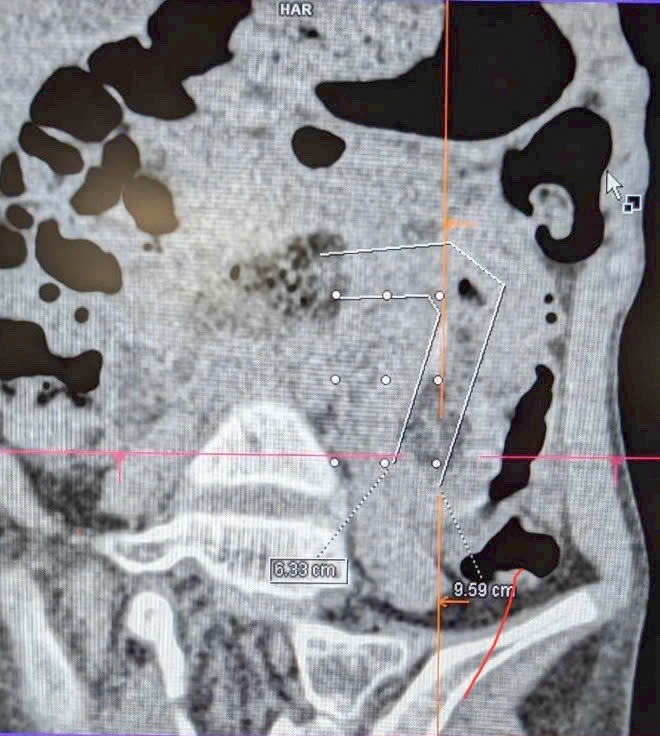

CT scan images confirmed the presence of the hairball and intestinal obstruction in the patient.